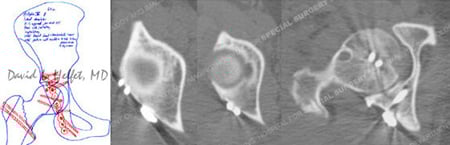

Pre-operative plan (left) and postoperative CT scan images (right) 1 day following ORIF.

A 64-year-old female was involved as a passenger in a high-speed motor vehicle accident while on vacation in Nicaragua. She was taken to a local hospital and diagnosed with a right-sided posterior hip dislocation that was closed reduced. She also had an associated right-sided Pipkin IV Type fracture of the femoral head with associated Posterior Wall Type fracture of the acetabulum. After placement of skeletal traction she was transferred to the care of Dr. David L. Helfet at the HSS Orthopedic Trauma Service through a medical flight facilitated through her travel insurance. Open reduction and internal fixation (ORIF) was performed through a Kocher-Langenbeck surgical approach with an anterior surgical hip dislocation. The Posterior Wall fracture was reduced and fixed with one-third tubular and pelvic reconstruction plates and screws. The femoral head fracture was reduced and fixed with sub-articular screws and preservation of the blood supply, reduction, hip stability, and adequate hardware placement was confirmed. At the time of her latest follow-up at 5 months radiographs reveal healed acetabular and femoral head fractures and maintenance of reduction with mild degenerative changes in the hip joint.